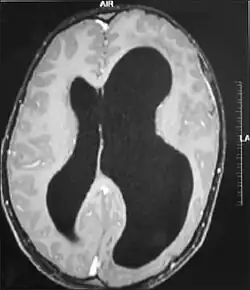

A megaloencefalia unilateral ou hemimegaloencefalia é uma malformação pouco comum caracterizada pelo crescimento anormal de um hemisfério do cérebro. Os meninos com este trastorno podem ter a cabeça grande, às vezes assimétrica. Sofrem com freqüência de convulsões intratáveis e de retardo mental. O prognóstico para os pacientes com hemimegaloencefalia é grave.